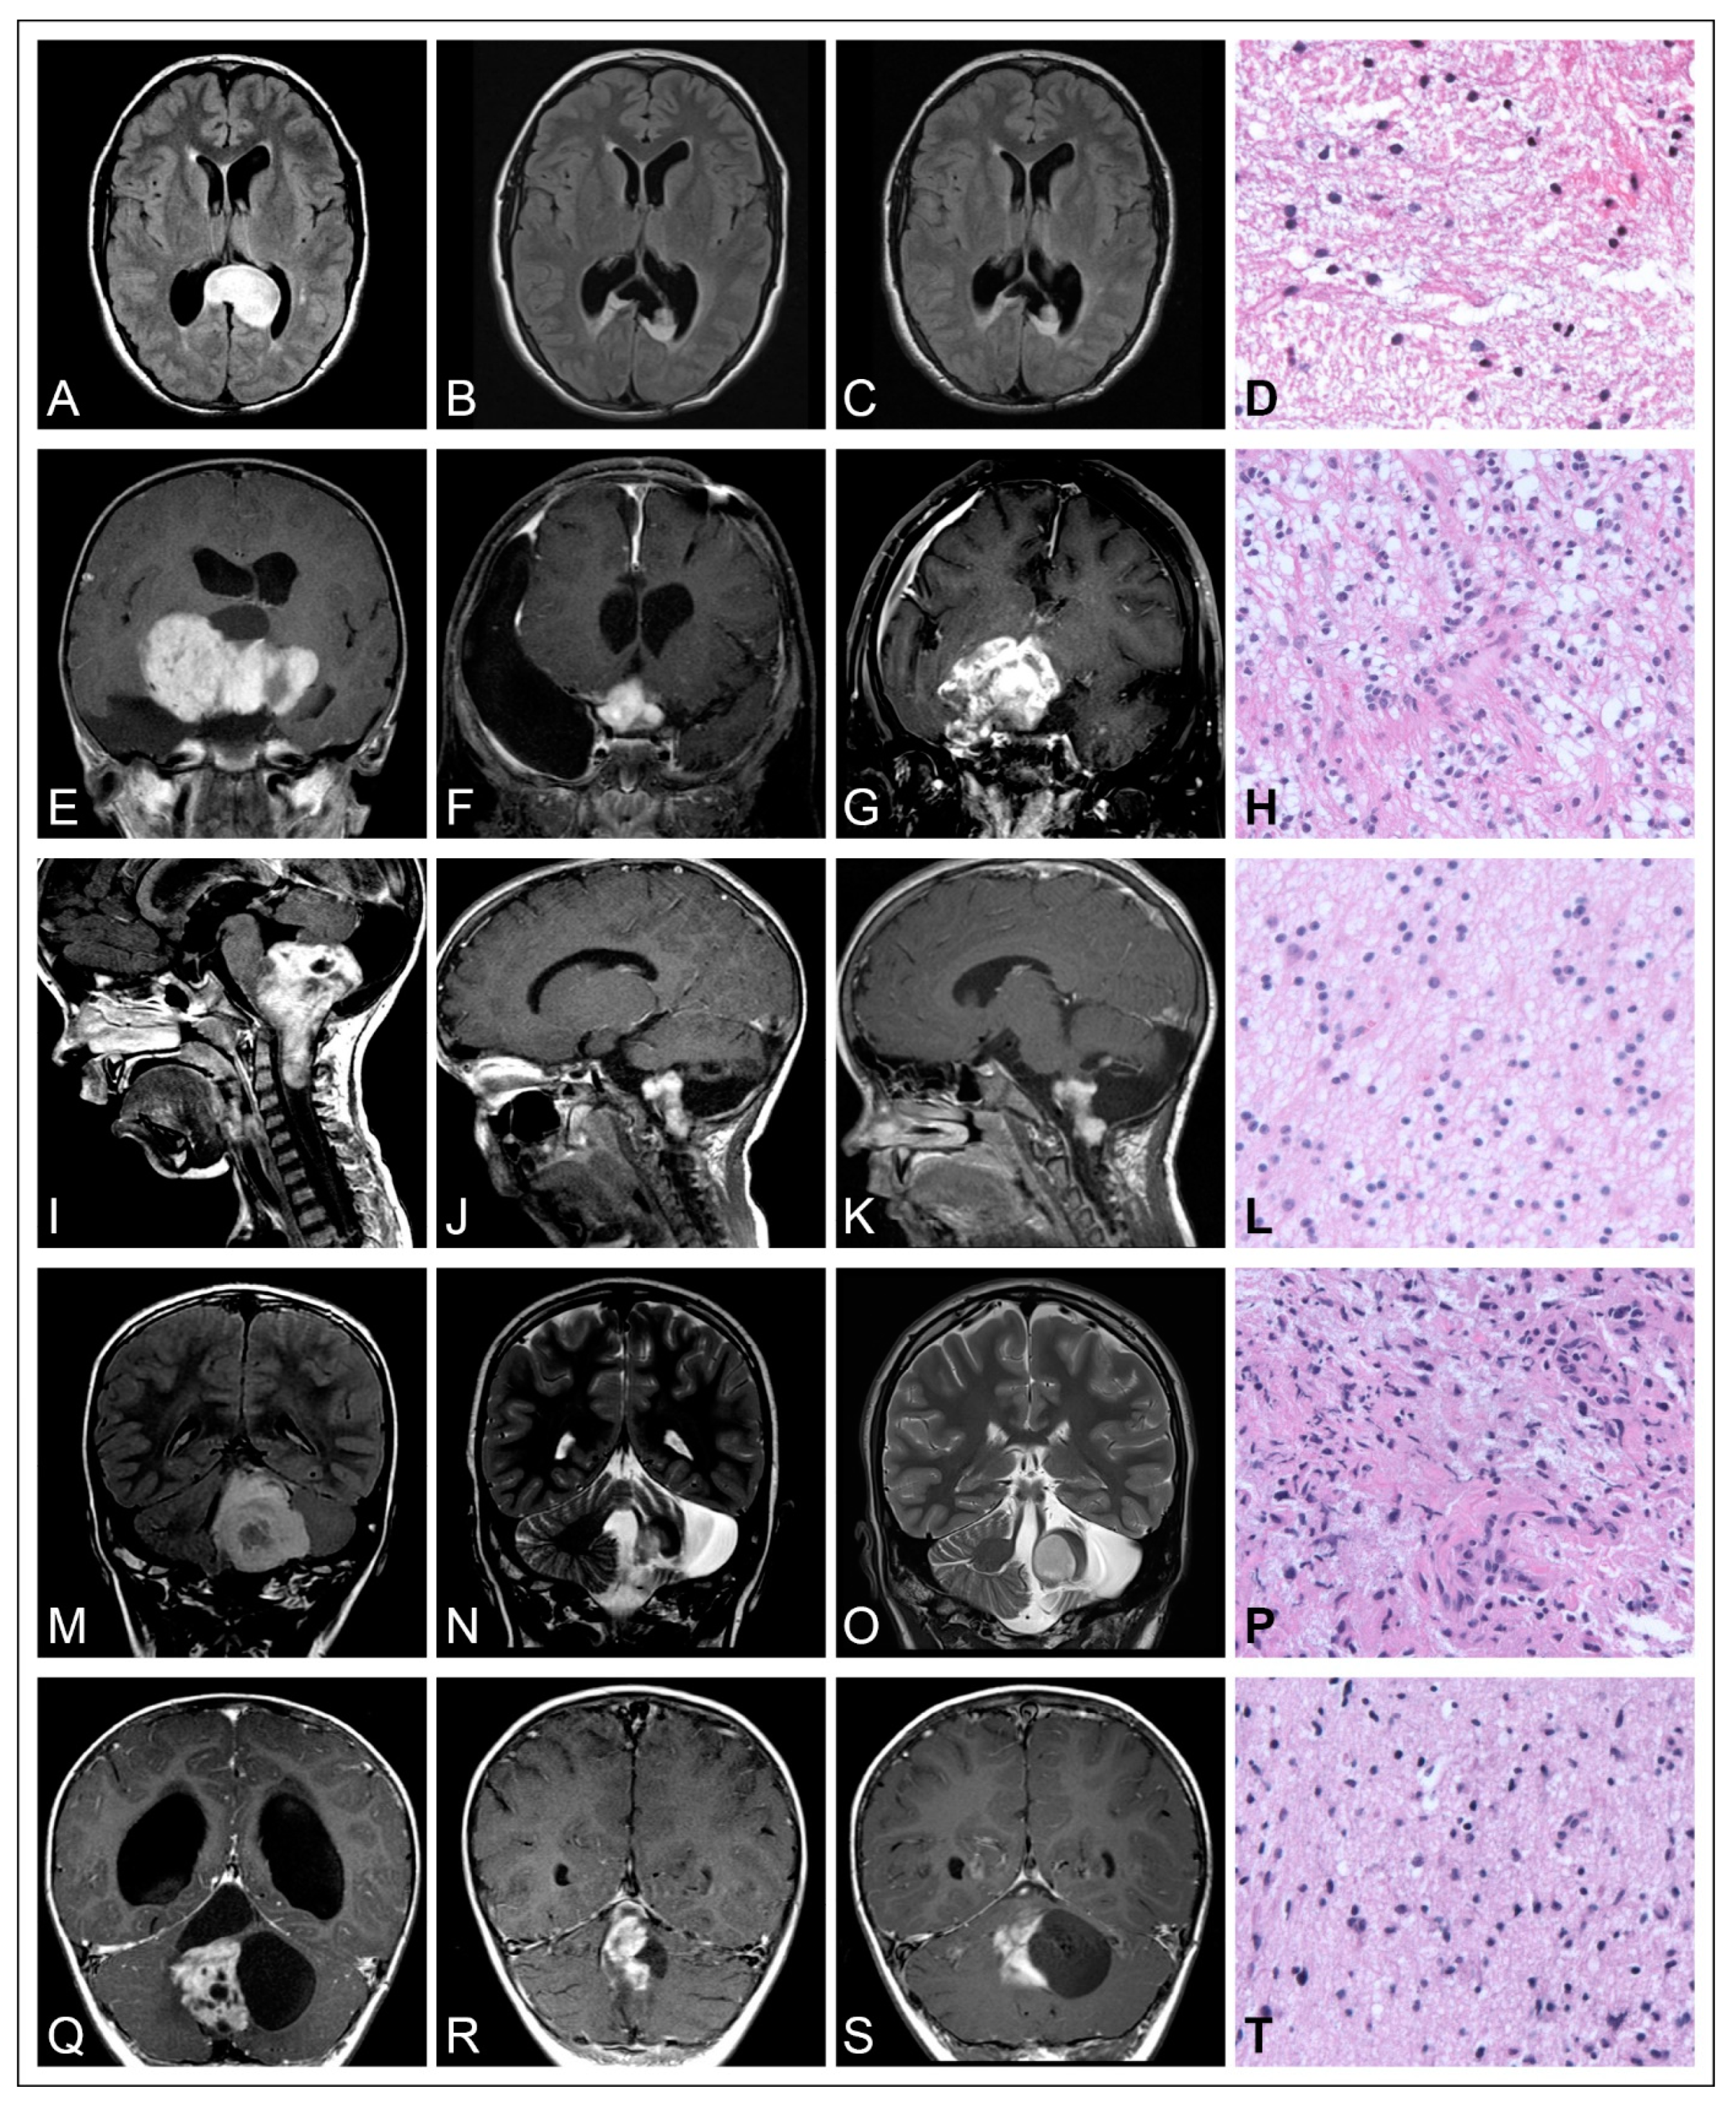

2.4. Histology